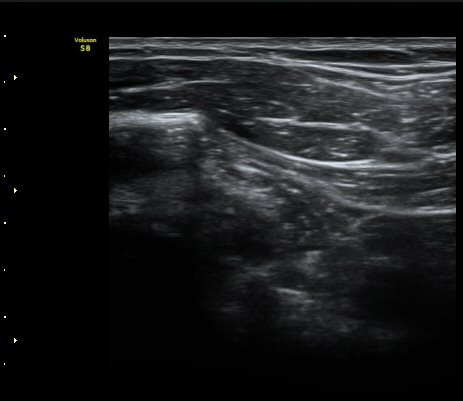

¿À±¸µ¹±â Á¾´Ü¸é°Ë»ç½Ã ¿À±¸ µ¹±â ³»Ãø, ¿À±¸µ¹±â ¾Æ·¡¿¡ ¼ö¾×Àú·ù°¡ °üÂûµÈ´Ù(±×¸² 5, 6).